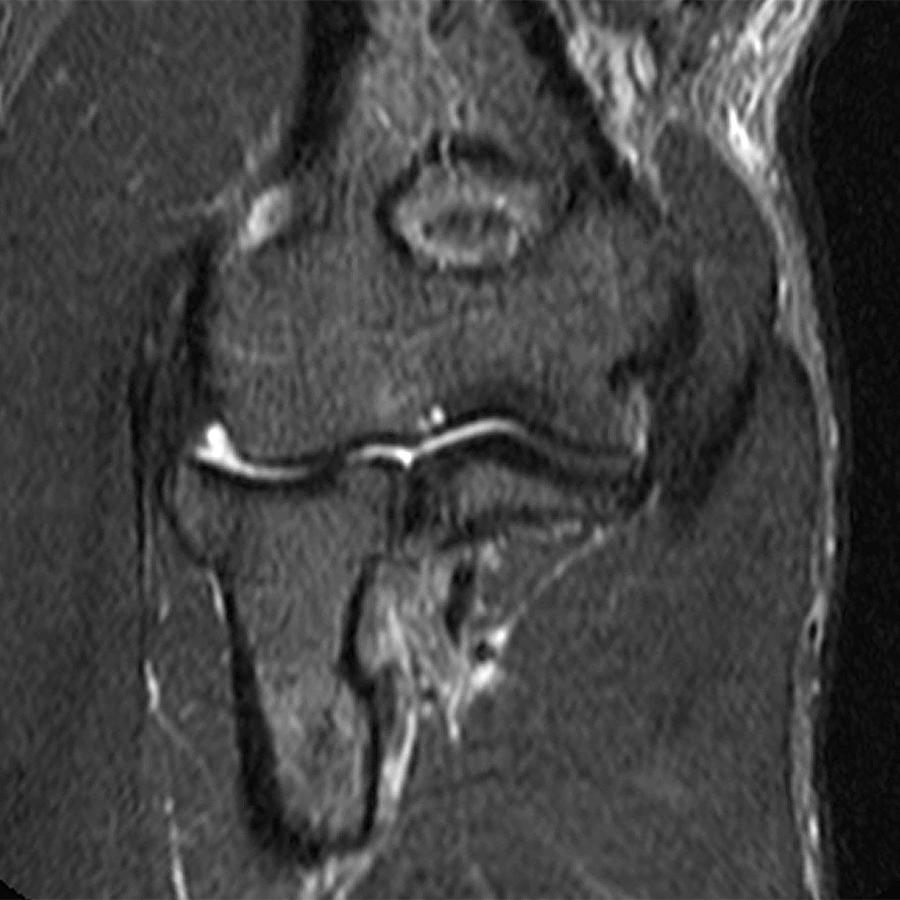

From radsource.us

Distal Biceps Tendon Rupture Elbow Radsource Pulled Tendon Elbow Find out the risk factors, clinical presentation, differential. Learn how to diagnose, treat and prevent elbow tendonitis with home remedies,. Tennis elbow is a condition that causes pain and weakness in the elbow, often from overuse of the muscles and tendons. Tennis elbow is a repetitive strain injury that affects the extensor muscle tendon on the outside of your elbow.. Pulled Tendon Elbow.